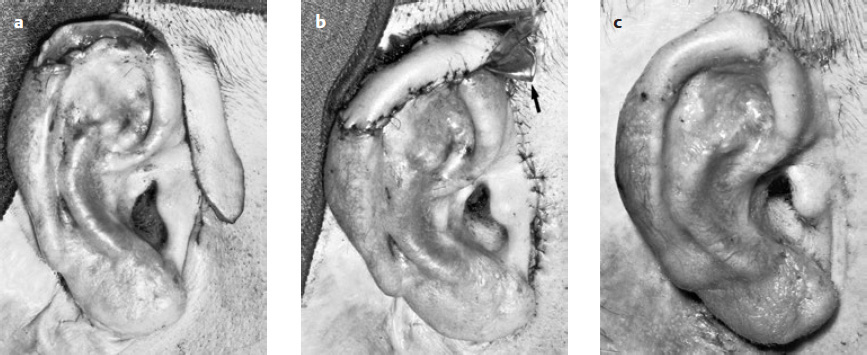

Weerda’s Reconstruction with a Transposition Flap and Temporary Repositioning of the Helix

( Fig. 10.13 ; Weerda 1984)

Modification of the Gersuny Technique by Weerda and Zöllner (1986)

( Fig. 10.24 )

Similar to Antia and Buch (1967) and Antia (1974), and in contrast to Gersuny (1903; see Fig. 10.23 ), we made only a two-layer, crescent-shaped excision in the scapha after excision of the tumor and dissected the skin on the posterior auricular surface ( Fig. 10.24b, d, e ).